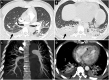

Various clinical presentations of the 2019 coronavirus disease (COVID-19) have been described, including post-infectious acute and fulminant myocarditis. Here, we describe the case of a young patient admitted for COVID-19-associated post-infectious fulminant myocarditis. Despite optimal pharmacologic management, haemodynamic status worsened requiring support by veno-arterial extracorporeal membrane oxygenation. Emergent heart transplantation was required at Day 11 given the absence of cardiac function improvement. The diagnosis of post-infectious COVID-19-associated myocarditis was made from both pathologic examination of the explanted heart and positive SARS-CoV-2 serology.